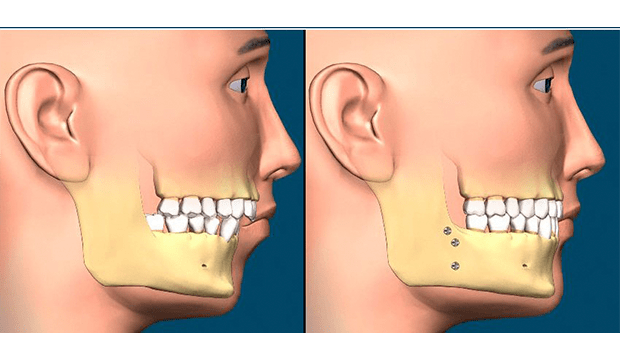

Çene cerrahı, çene kemiklerinde kesiler (osteotomi) yaparak çeneleri doğru pozisyona getirir. Çene hareketiniz tamamlandıktan sonra, kemikleri yeni (planlanan) konumlarına sabitlemek için kemik plakaları, vidalar, teller ve lastik bantlar kullanılır. Diş teli için kullanılan bir braketten daha küçük olan bu vidalar zamanla kemik yapısına entegre (kaynaşma) olurlar.

Bazı durumlarda çenelere fazladan kemik ekleme ihtiyacı olabilir. Bu durumda genellikle iliak adı verilen ön kalça kemiği bölgesinden kemik alınarak gerekli bölgeye plaklar ve vidalarla sabitlenir.

Tipik olarak, cerrahlar aynı ameliyat sırasında çeneyi değiştirebilir ve çeneyi yeniden yapılandırabilir. Cerrah çene kemiğinin ön kısmından bir parça keser, ileri doğru hareket ettirir ve plak ve vidalarla yeni konumunda sabitler.